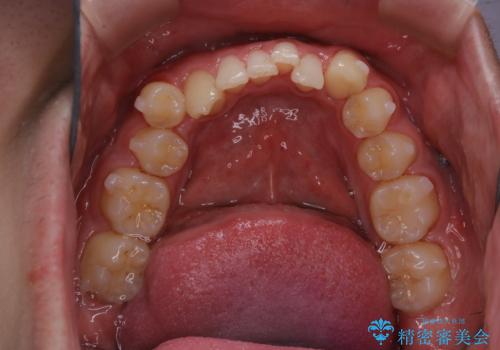

- マウスピース矯正中に、口臭が気になりクリーニングを行いたいとのことでした。染め出しをしての歯ブラシ指導とPMTC60分コースを行いました。

口腔内にはたくさんの細菌がいるため、ヌルヌルとしたプラーク(歯垢)が自然に歯の表面に付きます。

このプラーク(歯垢)にはたくさんの細菌が潜んでおり、虫歯や歯周病・口臭などの最大の原因です。そのため、毎日の歯磨きでプラーク(歯垢)をキレイに取り除くことが、健康な歯を保つためには欠かせません。

しかし、プラークは歯の色と似ているため、見ただけでは付着しているかどうかがハッキリとは分かりません。

染め出し液を使ってプラークを染め出すことにより、普段の歯みがきで磨き残している場所を目で確かめることができます。

日々の歯磨きを上達するには、まずどこが磨けていないか認識することが大切です。